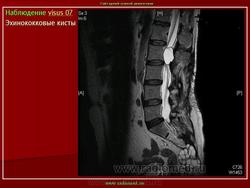

Магнитно - резонанснуютомография применяли на завершающем этапе неинвазивного диагностического обследования 13 больным эхинококкозом печени с целью детализации характера патоморфологических изменений в очаге поражения и уточнения степени вовлечения в процесс крупных сосудисто-секреторных структур.

Свободный выбор плоскостей изображения позволил уточнить топический диагноз. С другой стороны, благодаря высокому мягкотканному контрасту при МРТ выявили значимые дополнительные признаки паразитарных кист. Так, например, МРТ была наиболее информативной в выявлении неровностей внутреннего края кисты и начинающегося расслоения паразитарных мембран.

Несомненным преимуществом метода явилась возможность дифференцирования изменений в архитектонике печени с высокой разрешающей способностью. Вокруг гидатидных кист на МР -томограммах визуализировался ободок слабого изменения МР-сигнала (гипоинтенсивный на Т1 ВИ, гиперинтенсивный на Т2 ВИ) с нечеткими контурами, соответствующий перикистозным изменениям (рис 5а,б ). С помощью МР-волюметрии рассчитывали объем эхинококковых кист, объем непораженной паренхимы печени и степень выраженности компенсаторной гипертрофии органа. МРТ позволила диагностировать эхинококковые кисты в брюшной полости при сочетанном эхинококкозе без дополнительного контрастирования кишечника. При проведении МРТ были выявлены